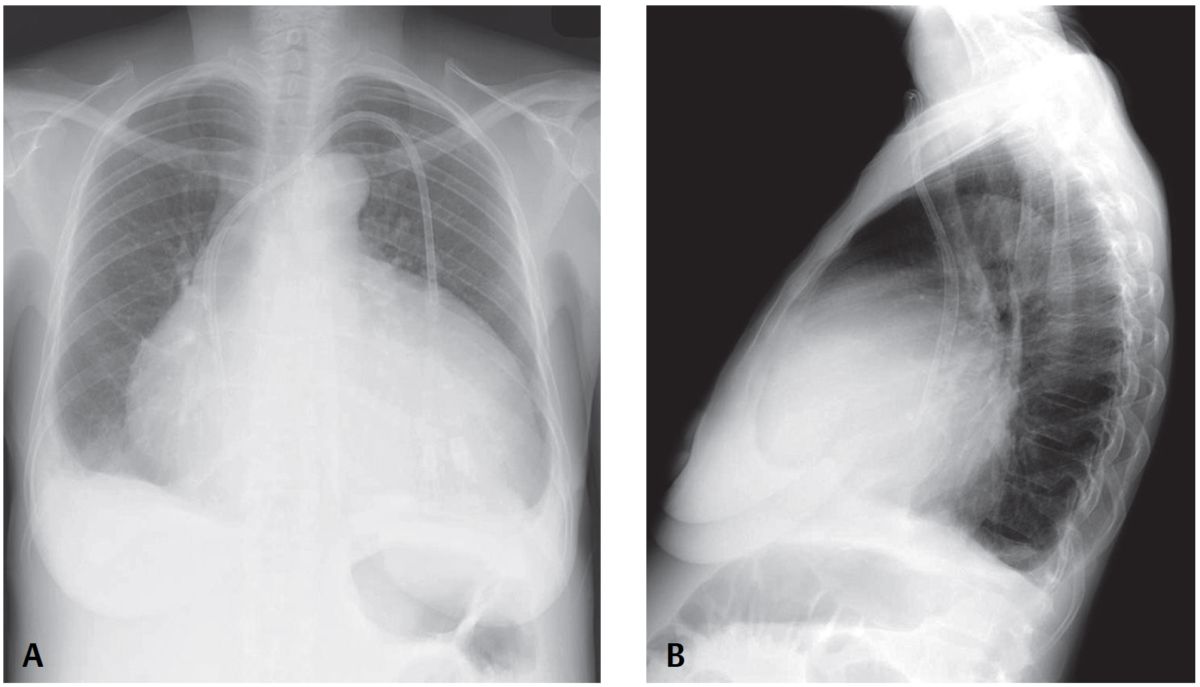

Uremia and Shortness of Breath Post category:Spot Diagnosis Post published:June 3, 2023 Share on Facebook Share on X (Twitter) Share on Pinterest Share on Email Share on Reddit Uremia and Shortness of Breath 40-year-old woman with long-standing uremia presents with increasing shortness of breath. What’s the Diagnosis ? FULL CASE AND ANSWER Share on Facebook Share on X (Twitter) Share on Pinterest Share on Email Share on Reddit Read more articles Previous PostAnisocoria from Nebulized Medication Next PostErythema and Swelling of Finger You Might Also Like Woman with Dermatomyositis and Subcutaneous Nodules on the Arms and Legs May 13, 2022 Infant with Nonbilious Vomiting and Lack of Stools June 11, 2022 Erythematous Concentric, Raised, Serpiginous Skin Lesions June 18, 2021